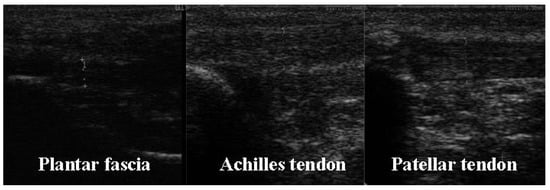

2.4.2. Ultrasonography